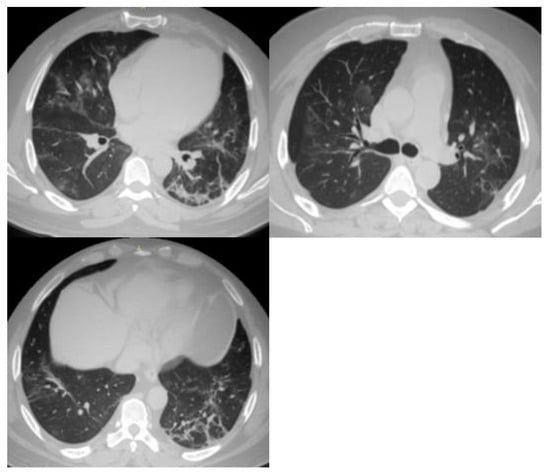

| 1 | Very low | Normal or non-infectious CT findings. |

| 2 | Low | CT findings incompatible with COVID-19: bronchitis, infectious bronchiolitis, and bronchopneumonia. |

| 3 | Equivocal/uncertain | CT findings of other viral pneumonia or non-infectious results: perihilar GGO, homogenous extensive GGO, and GGO with smooth interlobular septal thickening. |

| 4 | High | CT findings are similar to those for CO-RADS 5, but a lack of contact with the visceral pleura, located unilaterally, in a peri-broncho vascular distribution, or when the findings are superimposed on pre-existing lung abnormalities. |

| 5 | Very high | Typical CT findings: ground-glass opacities with or without consolidations in lung regions close to visceral pleural surfaces and multifocal bilateral distribution. |